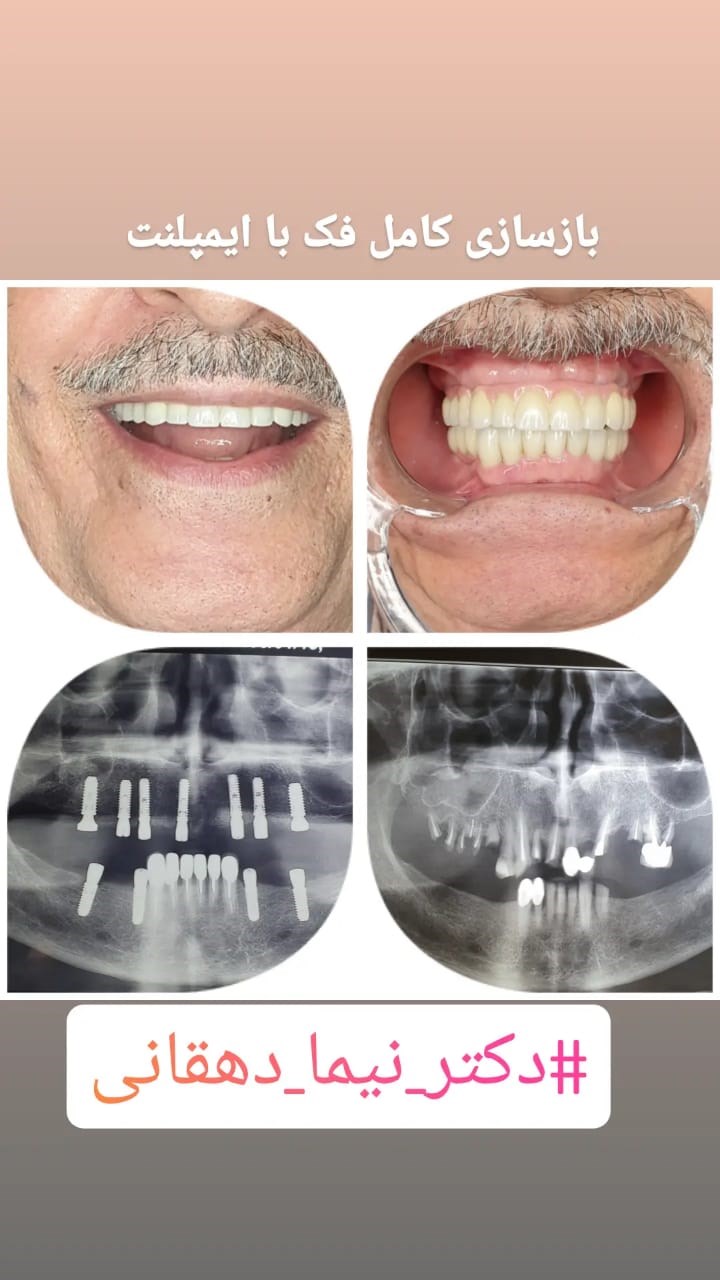

دکترنیما دهقانی

جراح دهان فک صورت

متخصص جراحی دهان،فک و صورت

✅ایمپلنتولوژیست